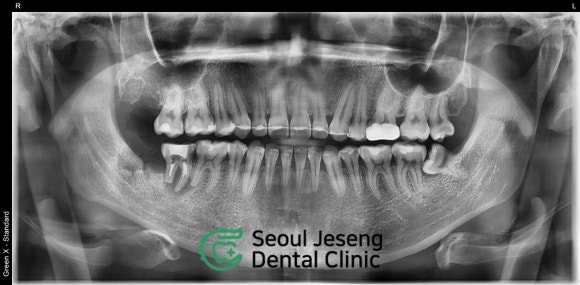

아침에 일어나니까

오른쪽 잇몸이 부어있었어요!

20대 남자 환자분

사진 상으로 좌측 아래를 보세요.

사랑니가 옆으로 누워있습니다.

그 앞에 있는 어금니의 뿌리는

칼로 자른 듯 똑! 끊겨있습니다.

뿌리 주위로는 까맣게 뼈가 녹아있구요.